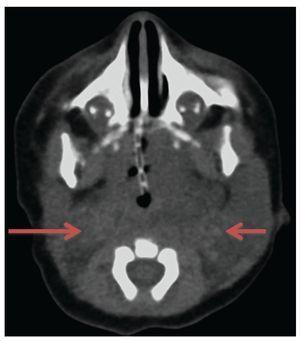

Laboratory studies, blood count, blood chemistry, blood gases and karyotype were normal. Computed axial tomography of the lateral neck showed clear asymmetry in volume with a left predominance at the expense of a hypodense, ill-defined image with apparent liquid attenuation. Vascular structures were shifted medially and later, anterior to the sternocleidomastoid muscle. In this image we observed parapharyngeal fat displacing the air space to the right. Compression and conditioning gauge decreased >50% (Fig. 2).

Figure 2 Computed axial tomography of the head and neck. Increased volume of the neck is observed predominantly on the left that displaces medial and posterior (arrows) vessels, anterior to the sternocleidomastoid muscle, with linear vascular hyperdense images in the interior. Reinforcement is not identified after administration of contrast medium.